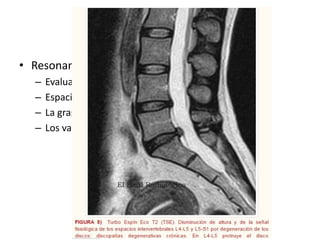

• Resonancia magnética

– Evaluar medula espinal

– Espacios meníngeos

– La grasa epidural

– Los vasos